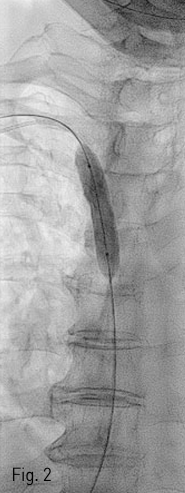

Fig 2

Percutaneous venoplasty was performed with 10mm x 4cm sized balloon catheter.